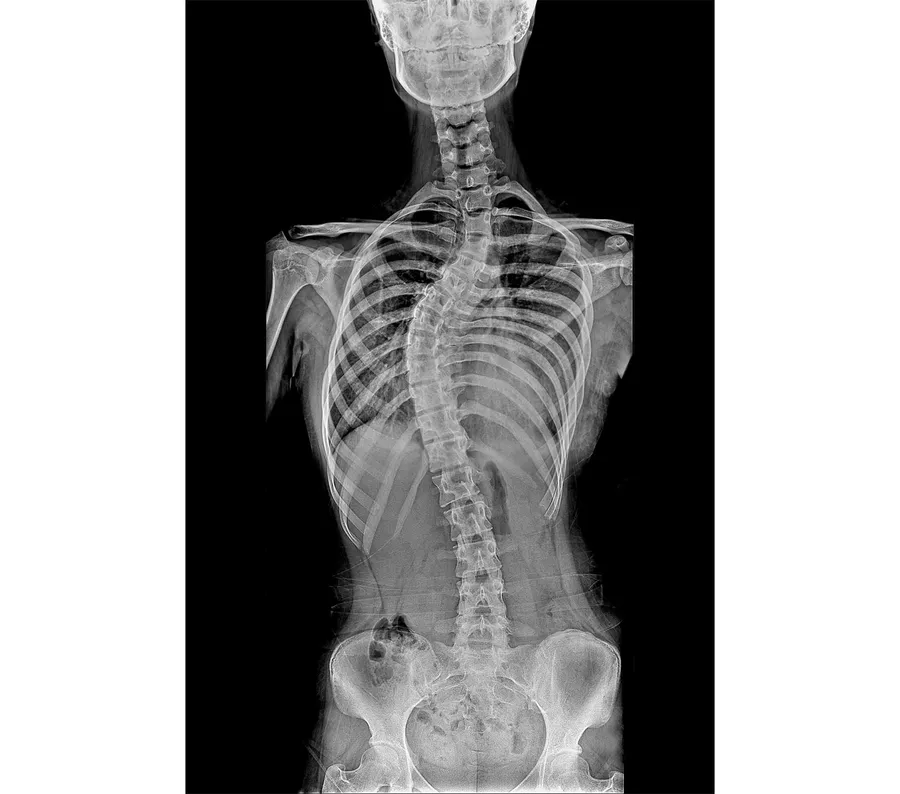

正常な脊柱は正面から見ると一直線であり、横から見ると頚椎と腰椎は前に曲がり、胸椎と仙椎部は後ろに曲がった形をしています。しかし、

脊柱側弯症は脊柱が正面から見て横に曲がった状態を指しますが、実際には単純な2次元的変形ではなく、脊椎の回転が伴い、横から見ても正常な曲がり方ではない3次元的変形が生じた状態を指します。脊柱側弯症は観点により様々に分類できますが、まず脊柱が横に曲がったものが一時的な変化か永続的な変化かに基づいて分類できます。